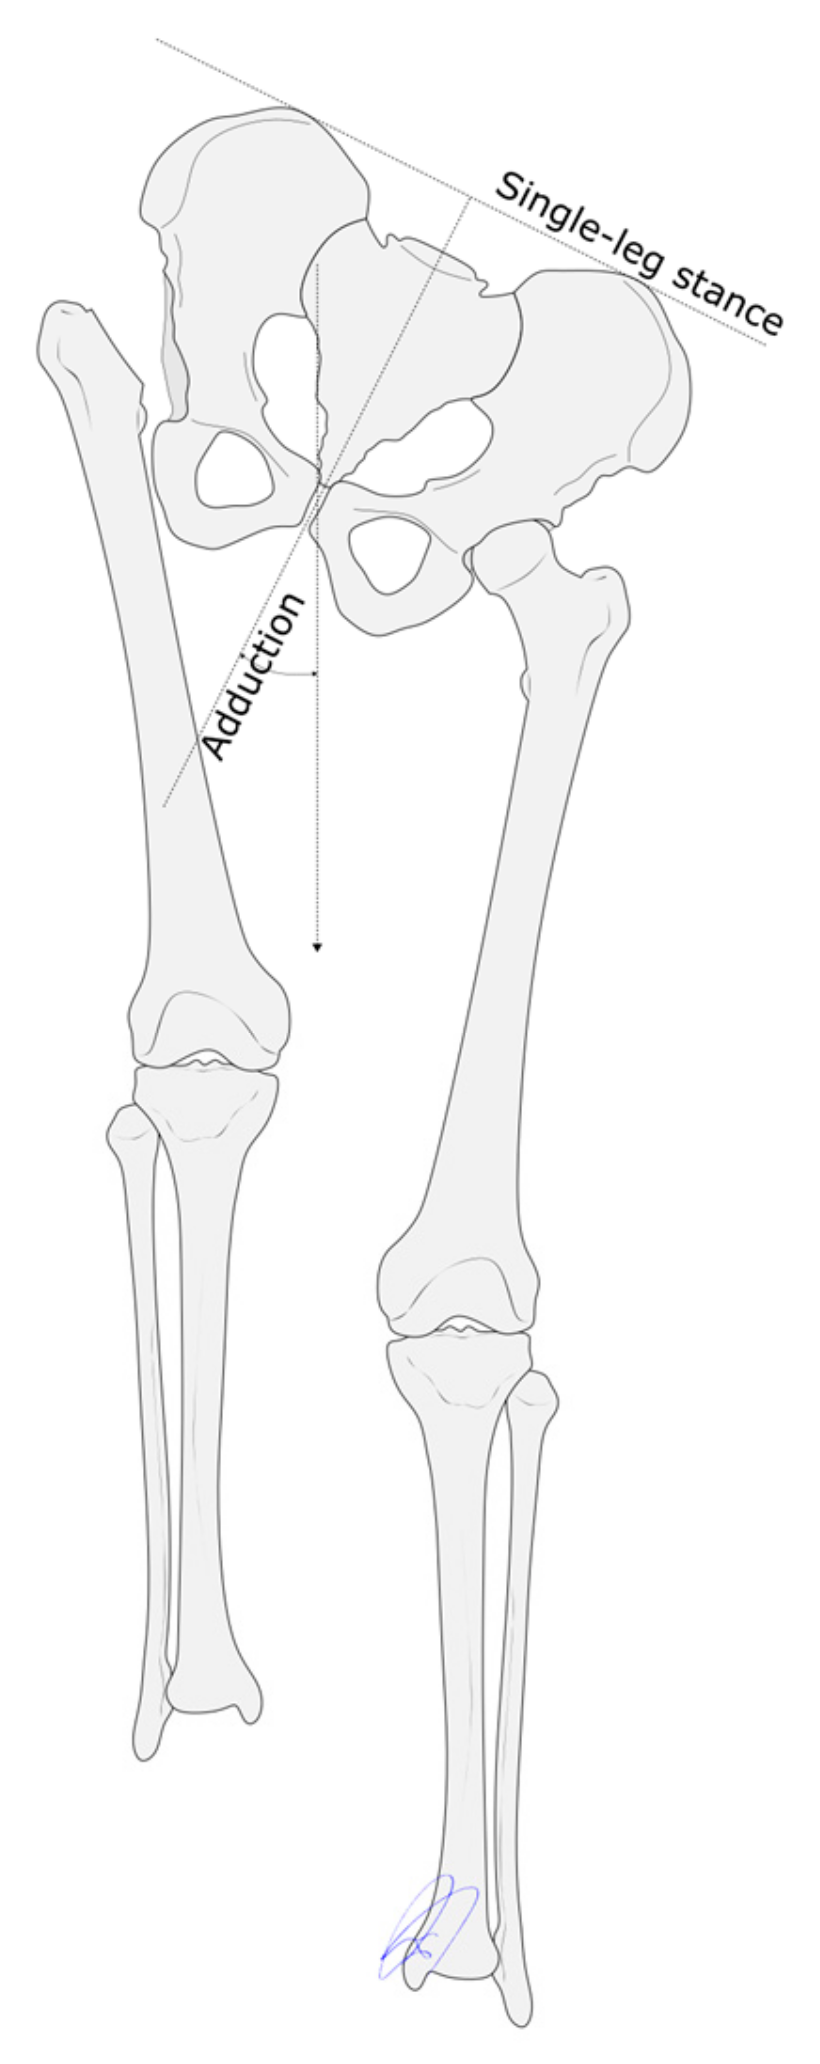

| Adduction | Preoperative | 12.5 | 0.003 |

| Follow-up | 22.5 |